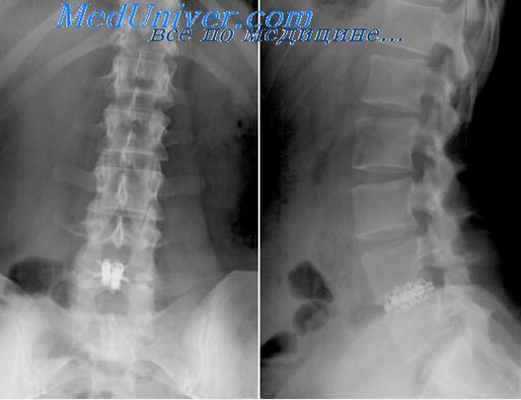

Гемиламинэктомия была проведена более чем у 50 такс. Гемиламинэктомия через мини доступ была проведена у 7 животных – такс, с грыжей диска на уровне от Th12 до L 2. Диагностировали грыжу по МРТ, КТ или миелографии в вентро-дорсальной и латеральной проекции. Для проведения минигемиламинэктомии, в настоящее время, на мой взгляд, более оптимально применять миелографию по сравнению с КТ и МРТ. Так как провести предоперационную миелографию с установкой маркера, для точной ориентировки при операции можно практически в любой клинике без последующей длительной транспортировки как в большинстве случаев бывает с томографией. Необходимо отметить, что для точного проведения гемиламинэктомии следует устанавливать какой-либо рентген-позитивный маркер (например, бельевую цапку) перед рентгенографией, для ориентировки во время операции. В этом случае миелография проводится непосредственно перед операцией. Это снижает вероятность ошибки в доступе к тем или иным позвонкам.

После миелографии забривалась шерсть над местом повреждения, этот участок обрабатывается антисептическим раствором. Цапка устанавливалась со смещением на 1-2 промежутка или краниально или каудально с жесткой фиксацией между остистыми отростками на уже выбритый участок. Проводилась еще одна рентгенография в латеральной проекции с маркером(цапкой).